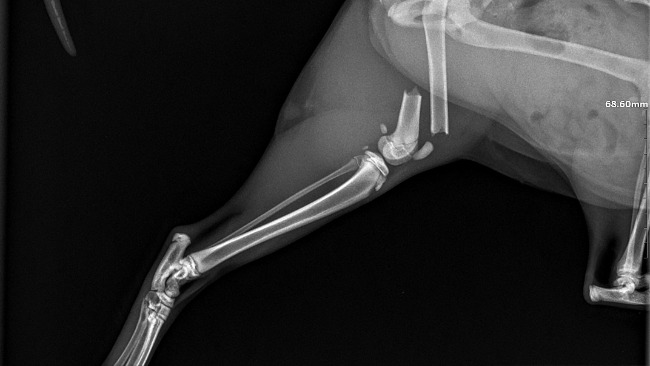

Przed nami konsultacja z prześwietleniem miesiąc po operacji — dokładnie 11 lutego — żeby sprawdzić, czy wszystko się prawidłowo zrosło i jak nasza bohaterka będzie funkcjonować na czterech, w pełni sprawnych łapkach.